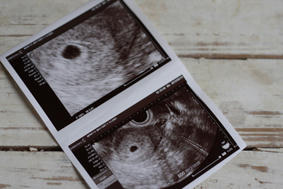

本日、病院に行ってきました。

赤ちゃんができてたーーーーーー

きたーーーーーーーーーーーっ。

本当に本当に嬉しいです。